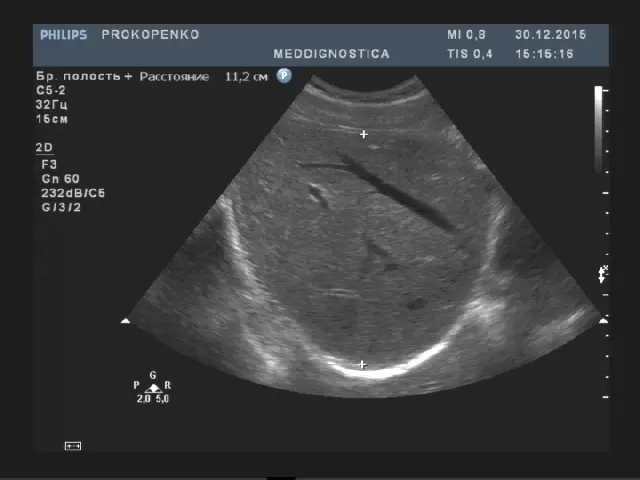

Товщина правої частки до 12.5см, товщина лівої частки до 6 см, товщина хвостатої частки до 3 см. Край лівої частки гострий. Поверхня гладка, ехогенність паренхіми середня, однорідна, звукопровідність не змінена. Капсула печінки чітко диференціюється. Судинний малюнок не змінений, не деформований. Воротна вена діаметром до 13мм, гілки ворітної вени: стіни не ущільнені, хід не деформований. Нижня порожниста вена не розширена, діаметр до 25мм. Холедоха діаметром до 7 мм. Лімфовузли воріт печінки не візуалізуються.

Патологічні зміни печінки, які виявляються на УЗД:

- жирова інфільтрація печінки (жировий гепатоз);

- гепатит;

- цироз;

- об’ємні утворення (кісти, гемангіоми, пухлини, метастази і ін.);